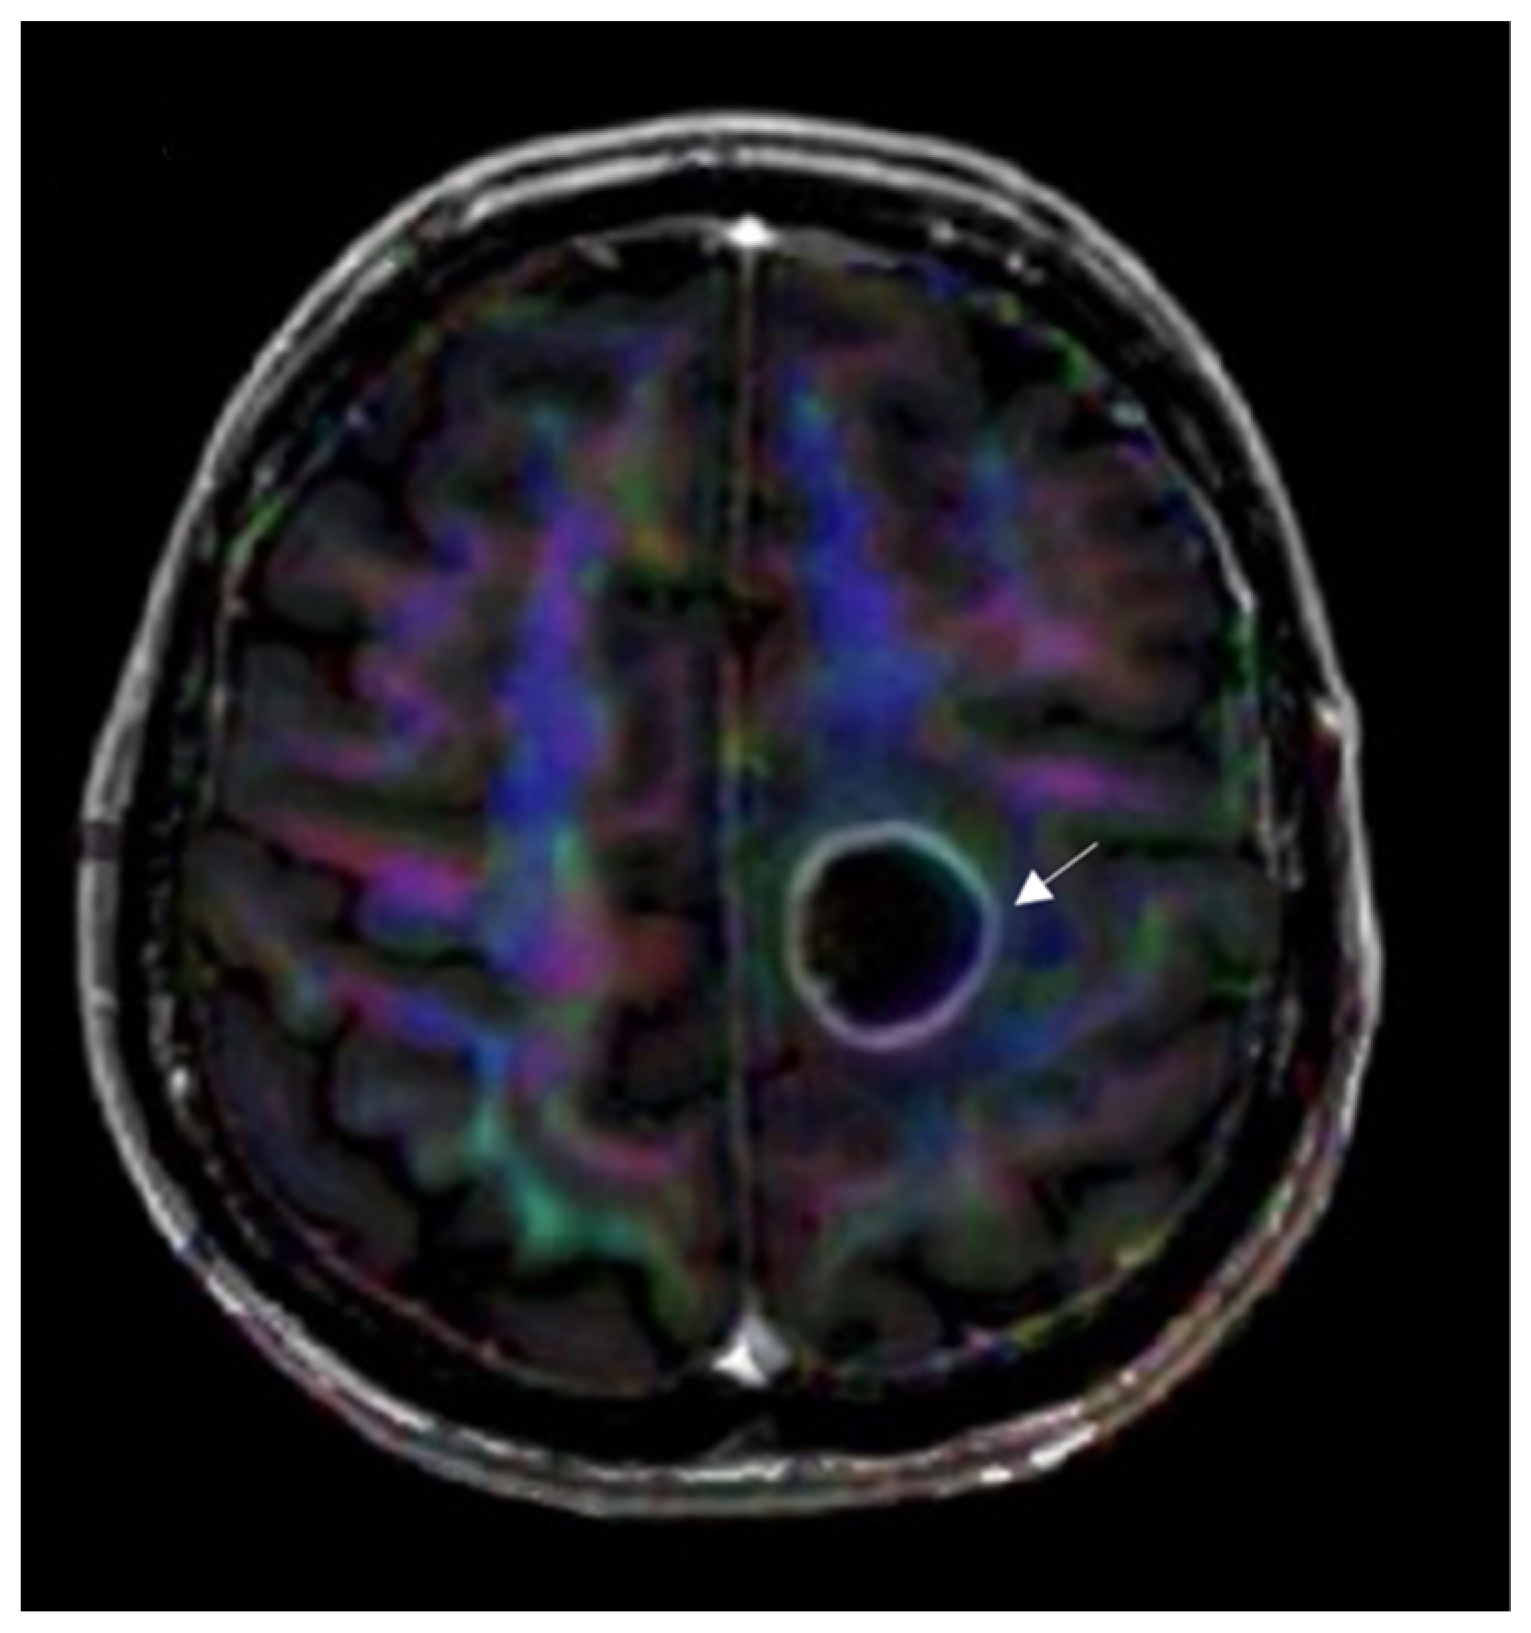

3.4.3. Diffusion Tensor Imaging

3.5. Nuclear Medicine Imaging